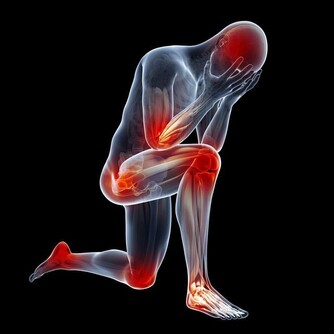

腳這個地方變黑,你就要小心了!!可能是癌症前兆…一定要注意了!!千萬不要忽視。。。。。。 小編就帶你一下你不知道的那些腳部信號的暗示以及一些需要注意的養生常識。看看以下哪些情況是你有過的吧。 1、足部的黑點 我們總是把皮膚癌和日曬聯繫起來,所以我們通常不會檢查腳上的黑點。然而,作為皮膚癌中最危險的黑素瘤,就可能發展到不經常接觸陽光的部位。黑素瘤甚至可能出現在腳指甲下面,看起來像是個黑點兒。 2、腳趾有「黑痣」 我們經常會在身體各個部位看到大小不同,甚至凹凸不平的黑點,這些黑點我們稱之為「黑痣」。腳趾上更是容易看到這些黑痣。那麼黑痣和癌症又有哪些聯繫呢?黑痣本身是天然無公害的,但是黑痣一旦惡化,演變成皮膚癌變將會危及我們的生命安全,即我們經常所說的癌變。 腳趾上的黑痣由於其特殊的位置就很有可能演變成為黑色素瘤。

惡性黑色素瘤是皮膚癌的一種,雖然在中國還不是很常見,但是在歐美地區卻是常見的惡性腫瘤之一。在我國不常見並不意味著黑痣對人體是無害的,近幾年來皮膚癌在我國的發病率也逐漸升高,所以我們還是需要了解其產生的原因,事先做好防護措施,防患於未然。 為什麼說腳趾上的黑痣更容易演變成癌症因子呢?因為黑痣在正常情況下癌變的機率是比較小的,但是如果經常遇到摩擦、擠壓,將會增大其癌變的可能性。我們的腳趾常年處於摩擦和擠壓的狀態下,所以更加容易造成癌變。 黑痣本身就是我們身體與生俱來的良性腫瘤。後天由於生活環境的影響以及自身各個器官的病變,導致了其進一步惡化為黑色素瘤。 還有一部分認為,黑痣只有在暴曬的情況下才會演變成黑色素瘤,但是我們正常情況下是不會暴曬到腳趾部位的。所以我們會容易忽略掉腳趾上的「癌症病毒」。但是,作為皮膚癌中最危險的黑色素瘤,是非常容易發展到不經常接觸陽光的部位。黑素瘤甚至可能出現在腳趾甲下面,看起來就像是一個普通的黑點。 所以如果腳趾部位出現黑痣的話,請大家要做好保護措施,經常觀察黑痣是否有異常變化,如果出現異常請儘快就醫。 3、勺子狀的腳指甲 有時對指甲的傷害或是長期接觸石油基質溶劑可能造成凹陷的像勺子一樣的腳趾形狀。同時,缺鐵也可能會形成這種特殊形狀。